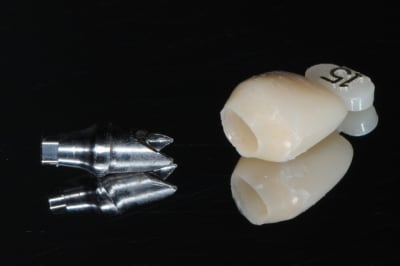

1-2-3-4-5: façonnage de l'émergence prothétique

la suite demain...

5-6-7: pilier esthétique zircone et validation

8: transfert de pilier pop-in pour l'empreinte (j'adore ce système)

9: gencive gingifast sur maitre modèle

1-2: l'ensemble prothétique; pilier-vis-couronne